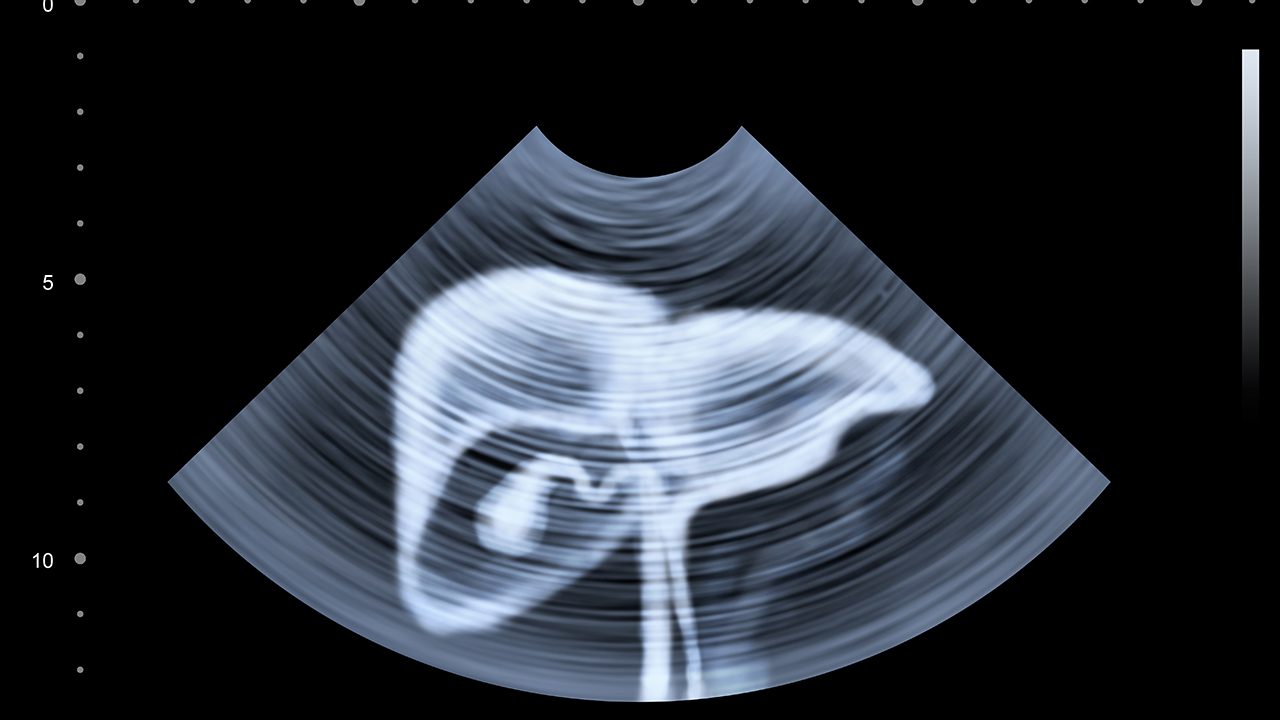

肝癌是一种常见的恶性肿瘤,其发病原因复杂,包括病毒性肝炎、肝硬化、长期酗酒等。早期诊断和治疗对提高患者生存率至关重要,因此选择一家专业的医院进行治疗尤为关键。

肝癌的预防与健康管理至关重要。建议高危人群定期进行肝脏超声和甲胎蛋白检查,做到早发现、早治疗。日常生活中应避免酗酒,注意饮食卫生,接种乙肝疫苗,控制脂肪肝。对于慢性肝病患者,要定期随访,规范治疗基础肝病。保持良好的生活习惯和积极乐观的心态,有助于降低肝癌发病风险和提高治果。